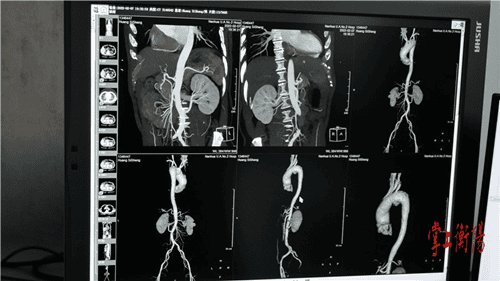

据悉,患者所患的是胸主动脉假性动脉瘤,病变累计供应头颅血运的弓部主动脉,随时有血管破裂大出血死亡风险,这种疾病是血管外科最为凶险、复杂的疾病。常规的开放手术需要开胸及体外循环,创伤大、并发症发生率高,对患者损伤较大。若采用介入技术,患者的弓动脉瘤足足有3公分大,由于弓部有重要分支血管,腔内治疗面临着巨大的挑战,稍有差池都可能影响大脑血供、导致脑梗等严重后果。最终,南华附二医院血管外科团队经过反复推敲和论证,在上海长海医院专家的远程会诊指导下,决定采用体外预开窗的方式,术前根据影像资料确定病变部位与分支血管之间的关系,体外将预制支架部分释放,精准定位后在支架上预先开好两个窗用来重建颅内两分支血管,术中准确释放支架,保证支架和窗口的精确对应,保障大脑血运不受影响。